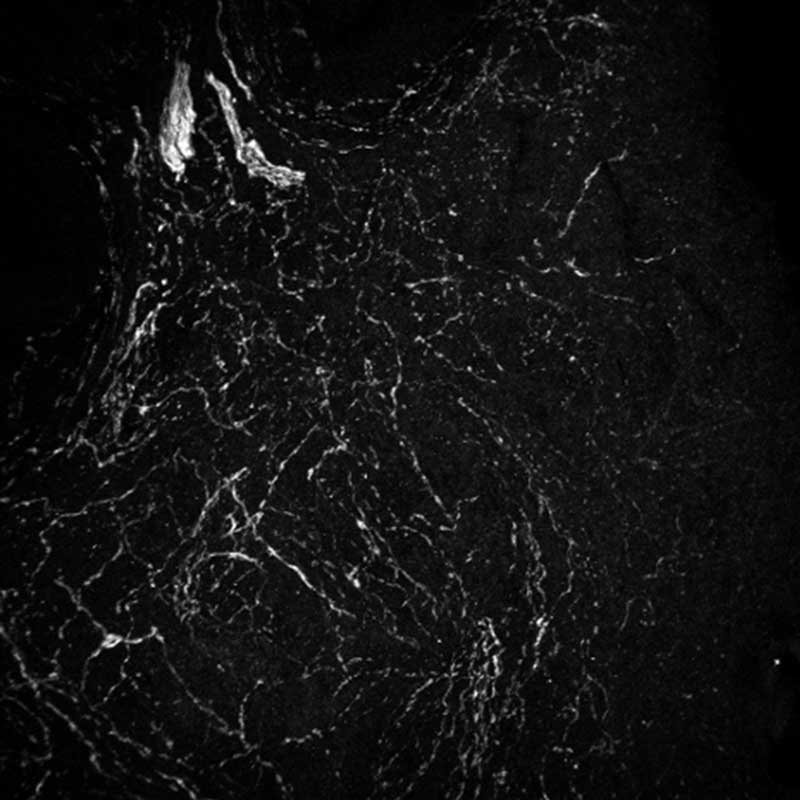

A human ovary at age 23 (left) and age 55 (right). Sympathetic nerves, involved in the “fight or flight” response, are shown in white and increase with age. Images by Gaylord, et al.

A microscopic image showing few sympathetic nerves in an ovary at 23 years of age.

A microscopic image showing a larger presence of dense sympathetic nerve cells in an ovary at age 55.